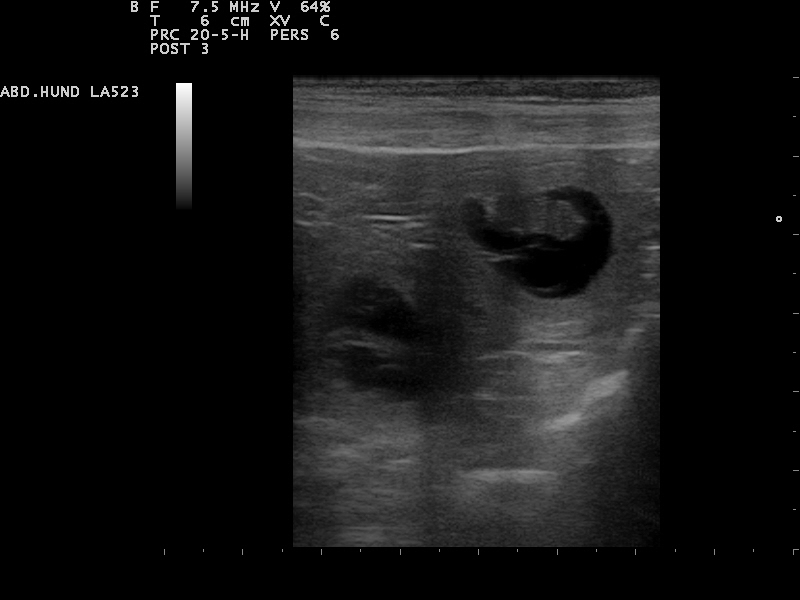

Am 22. Tag sind die Embryonen sichtbar. Der Herzschlag kann zur Diagnose der Trächtigkeit herangezogen werden. Anstrengende Aktivitäten sind

15.12.2015 jetzt zu vermeiden.Die Proteinzufuhr im Futter kann erhöht werden. Hierfür eignet sich sehr gut die Gabe von Welpenfutter. Zu diesem Zeitpunkt kann

mit einer Ultraschalluntersuchung der Zustand der Trächtigkeit festgestellt werden. Besprechen Sie mögliche Risiken einer solchen Untersuchung mit dem Tierarzt.

22.12.2015 Dies ist der beste Zeitpunkt, um die Trächtigkeit anhand des Herzschlags zu diagnostizieren.

Die Embroynen sind etwas walnussgroß und sind gleichmäßig im Uterus verteilt.

Die Ultraschall-Untersuchung hat ergeben das Alexa trächtig ist und wir gespannt auf

unseren B-Wurf warten können

Das sind die ersten Bilder unseres B-Wurfes